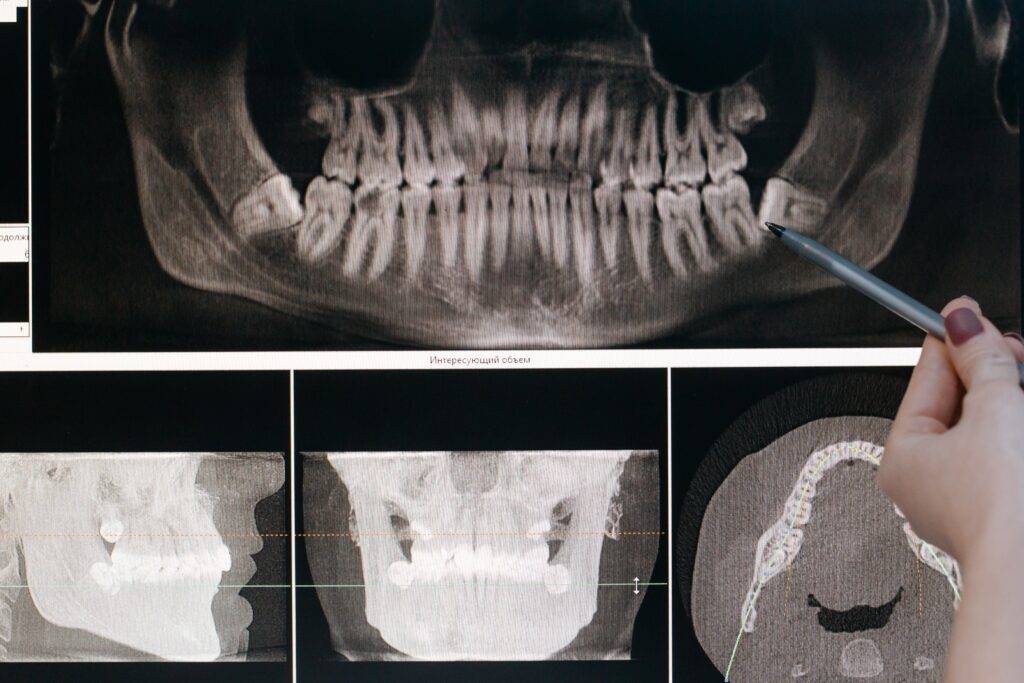

Are 3D Dental X Rays Necessary? MartLabPro Are Yearly Dental X Rays Necessary In a piece titled too much dental radiography, sheila feit, a retired medical expert based in new york, pointed out that using x. Adults who properly care for their teeth and have no symptoms. For children and teenagers, dental. Adults with good oral health: Adults with past dental problems: Are Yearly Dental X Rays Necessary.